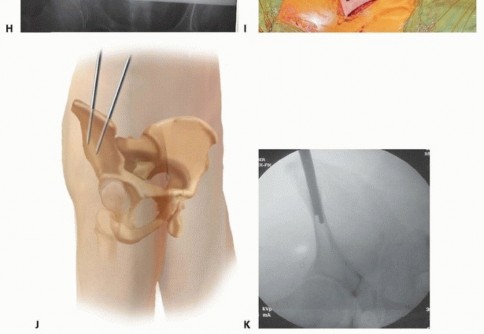

This requires that the drill be held more cephalad (directed caudad) than expected to allow proper position within the desired supra-acetabular bone (superior and cephalad to the acetabulum) rather than the thin bone of the ilium. Triple cannulated drill sleeves are used to protect soft tissues. The fixation pin is inserted, allowing the cortical walls of the ilium to establish direction. An image intensifier may aid in elective nonemergent fixator application. 2. ## Supra-acetabular Technique The patient is positioned supine on a radiolucent table. Safe introduction and proper positioning of the pin require the assistance of fluoroscopic guidance. The open approach for pin placement begins with a vertically oriented 5- to 10-cm incision, depending on patient body habitus and prereduction pelvic deformity. A smaller transverse incision has been described in addition to entirely percutaneous techniques of pin insertion. This vertical approach begins along the lateral border of the anterior superior iliac spine, extending distally and lateral to the AIIS. The interval between the sartorius and tensor fascia lata is identified ( TECH FIG 4A). Tissue planes are developed with blunt dissection and the anterior inferior spine is palpated. The lateral femoral cutaneous nerve is most commonly identified medial to the anterior iliac spine. Anatomic studies have demonstrated the lateral femoral cutaneous nerve to have a variable course, often within 10 mm of inserted pins. 6 With blunt dissection and the use of protective drill sleeves, the lateral femoral cutaneous nerve may be adequately protected. Supra-acetabular pins should be inserted no less than 2 cm proximal to the joint to avoid intra-articular penetration. Capsular extension of the hip may be up to 16 mm superiorly.

An obturator oblique view with slight cephalad angulation

(obturator outlet view) is first obtained. A metallic marker is positioned 2 cm proximal to the hip joint under fluoroscopic control ( TECH FIG 4B). The trocar assembly is positioned under fluoroscopic control superior to the hip joint. Only the outer cortex is drilled. A triple cannulated guide facilitates atraumatic drill and pin insertion. The drill, followed by the pin, is directed within the pelvis, avoiding intra-articular penetration of the hip joint.

Pin angulation is typically 20 degrees medial from the vertical axis and slightly cephalad. The drill is directed toward and superior to the sciatic notch (30 to 45 degrees in the sagittal plane). Fluoroscopic guidance (iliac oblique view with slight cephalad angulation) ensures proper pin trajectory and depth of insertion ( TECH FIG 4C,D).

---

TECH FIG 4 • Supra-acetabular pin insertion technique. A. The interval between the sartorius and the tensor fascia lata is established (lateral femoral cutaneous nerve protected [

asterisk

]). B. An obturator outlet view identifies the proper pin entry site. C,D. An iliac oblique view with cephalad angulation directs the advancing pin. E,F. The rollover view (obturator oblique inlet view) ensures pin placement within the inner and outer tables of the pelvis. Intercortical pin orientation within the tables of the pelvis is monitored on an obturator oblique inlet view (“rollover view”) ( TECH FIG 4E,F). A 5-mm diameter, 50-mm thread length pin is inserted to the depth of the threads. A second pin may be inserted proximal to the first, if desired. 3. ## Frame Application and Reduction No frame, regardless of complexity, restores sufficient definitive fixation to vertically unstable lesions. 22 Accordingly, simple constructs are preferred to permit patient mobilization, abdominal access, and performance of subsequent diagnostic and therapeutic procedures. Accurate pin placement within the curved iliac crest mandates a nonparallel converging pin pattern. Pin clamps with a straight configuration require that pins be prestressed to conform and accommodate such clamps ( TECH FIG 5A). Those with an independent ball joint design offer an attractive alternative (TECH FIG 5B). 319